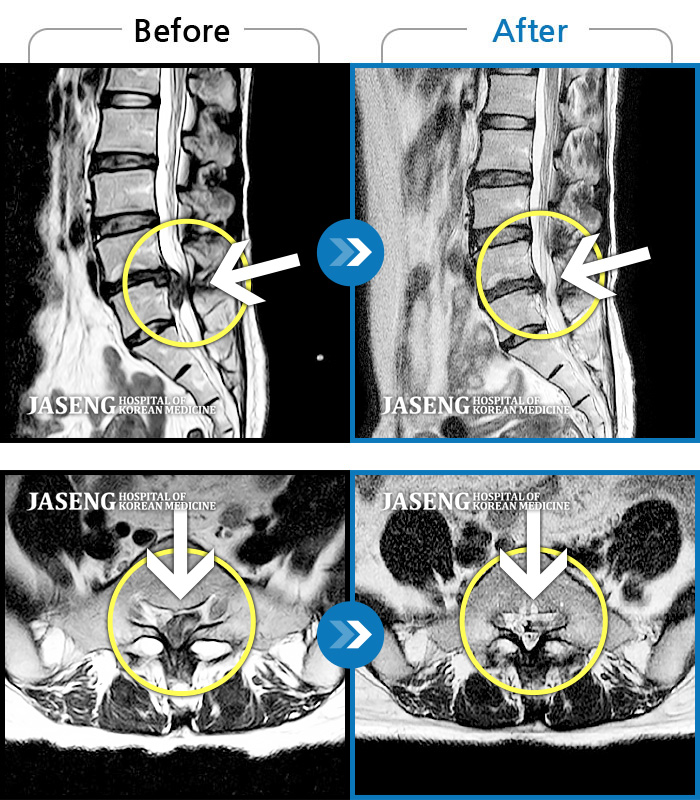

허리통증, 골반 저림, 발가락 근력저하가 심하여 일상생활이 불가능한 상태

2023.05.19 ~ 2023.10.14